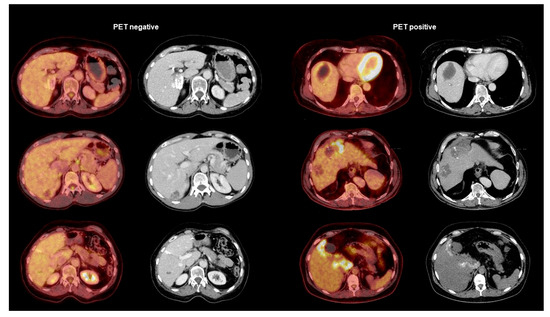

2.5. PET/CT Study

3.3. Biomarkers in Relation to PET/CT Results